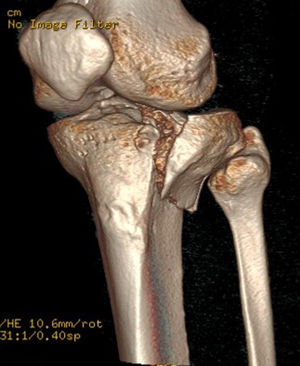

Several classifications of tibial plateau fractures exist, based on their location and displacement. The most widely used is the Schatzker classification, which divides fractures into 6 types, ranging from the least to the most severe. The AO classification is the most extensive, corresponding to 41 A-B-C. Luo's three-column classification is the simplest for surgical planning purposes. In all epidemiological studies, the most frequent fractures are Schatzker type 2 or AO 41B3. These correspond to an external unicondylar fracture pattern caused by a valgus mechanism involving depression and a vertical fracture line.1–7 The advent of CT and 3D models has greatly contributed to the description of different fracture patterns for adequate surgical planning,1–6 with the posterolateral area being described as having the highest incidence of fracture lines and poor reduction2,6 (Fig. 1).

In the CT study, volumetric acquisition was performed using a multi-slice scanner at .6mm thickness, followed by multiplanar reconstruction at 1.5mm slice intervals. In coronal plane reconstruction, the point of greatest fracture depression in millimetres, corresponding to the maximum joint step, and the maximum width/transverse diameter in millimetres were analysed. In the sagittal plane, the maximum anteroposterior joint step diameter in millimetres and the maximum external tibial plateau slope in degrees were measured (Fig. 3). Post-processing in the axial plane involved delimiting the fracture contour and calculating the affected area in cm2, as well as determining the maximum anteroposterior and transverse diameters in mm (Fig. 4).